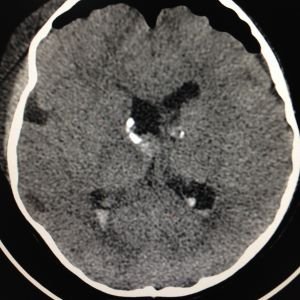

ESCLEROSIS TUBEROSA